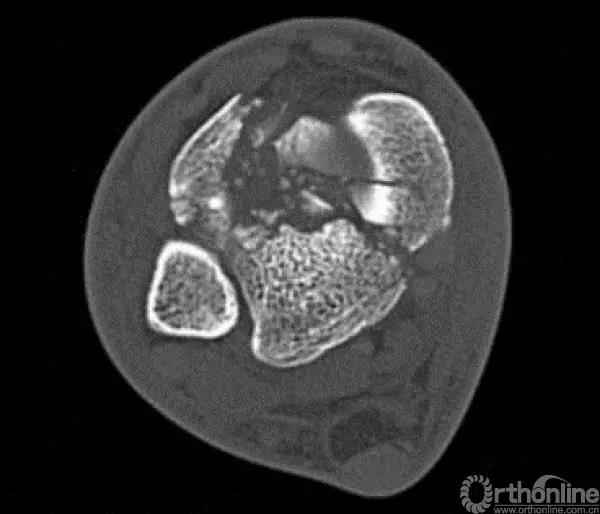

他将pilon骨折大致的骨块进行了分类,分别为后、前内、前外三个骨折块。Pilon骨折的入路一共有5个,前内、前正中、前外、后内、后外。

2.中心粉碎骨折

对于中心粉碎骨折需要充分牵引、撑开,将关节面的骨折块先找到摆放在合适的位置,用克氏针将关节面的骨块应用排筏技术先固定好,从下方观察关节面的复位情况,并且确认骨块不会向上推起,适当植骨,然后将骨块前后和左右进行压实后进行固定。